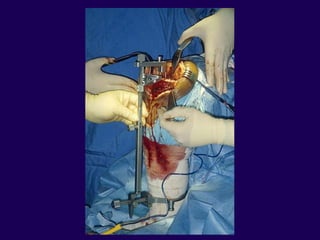

Surgical Technique

Incision — straight longitudinal

incision

Tissue handling key

Avoid flaps

Preserve soft tissue flap about the

patella